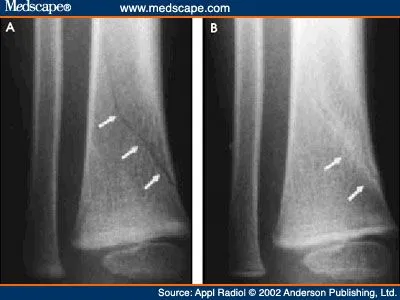

Image result for toddler fracture

Subtle toddler fracture